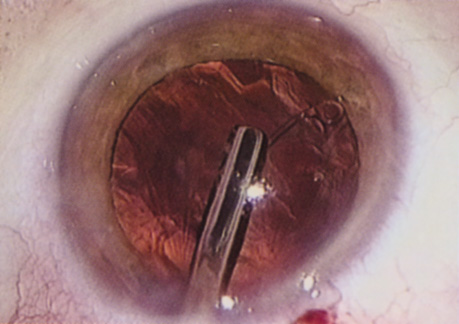

Many patients are most bothered by cataract-induced glare. For these patients, acuity testing under glare situations is indicated. There are several methods to assess visual acuity reduction by glare. The choice of method is often best dictated by the patient's history. If a patient complains of glare problems in the supermarket, or other uniformly illuminated environment, the brightness acuity test can be performed (Mentor Ophthalmics). For this test, the specially illuminated handpiece is held in front of the tested eye using best spectacle correction (Fig. 1). The Snellen acuity is rechecked and can be recorded on each of three light settings.